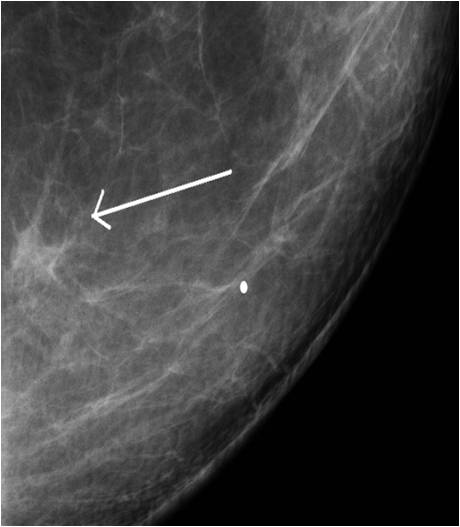

Star-shaped lesions are very typical of malignant tumors.

o “White star”: describes the tumor body with dense spiculations of various lengths appearing around the core = carcinoma

o “Black star”: there is no tumor body, the central part is transparent. The spiculations are arched, long and thin. These usually do not indicate the entity of the lesion; they can either be benign or malignant. Examples are lobular carcinoma, post-radiation scar tissue, fatty necrosis or postoperative scar tissue (patient history is indicative!).

Image

Picture 13.

Picture 14.

Picture 15.